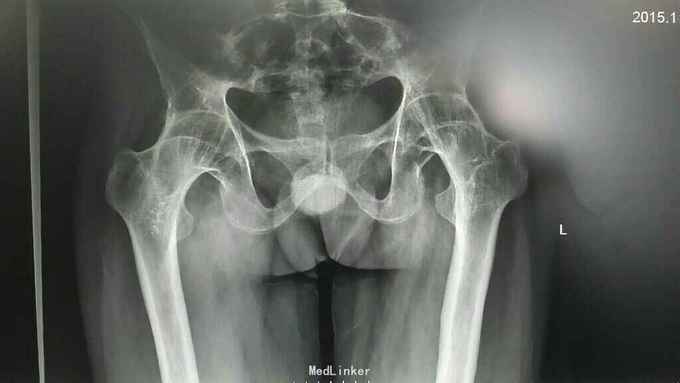

患者男,41岁。 主诉:双髋关节疼痛伴活动受限15年 现病史:15年前无明显诱因出现双髋部疼痛,轻微活动受限。至当地医院确诊为“强直性脊柱炎”,因经济原因未予正规治疗。近年来,症状进一步加重,出现双髋关节强直,生活无法自理。(可怜天下父母心,每天都是父母给他洗脚,系鞋带,轮椅带着他出去散心。这一次父亲带着他来看病,也是拼凑很长时间,说了一句让我心酸的话:我们都老啦,不能一辈子给你洗脚,系鞋带啊,你做了这个手术起码自己能照顾自己啦,我们走了也能合眼啦。)带着复杂的心情,我接诊了这个病人。

患者双髋关节完全强直,髋关节屈伸活动度0度。双髋关节屈曲畸形约30度。腰椎轻微后凸畸形,略活动受限。颈椎活动可,无明显颈胸椎后凸畸形,胸廓活动度无明显受限。 患者一般情况可,无高血压,冠心病,糖尿病等慢性病史。